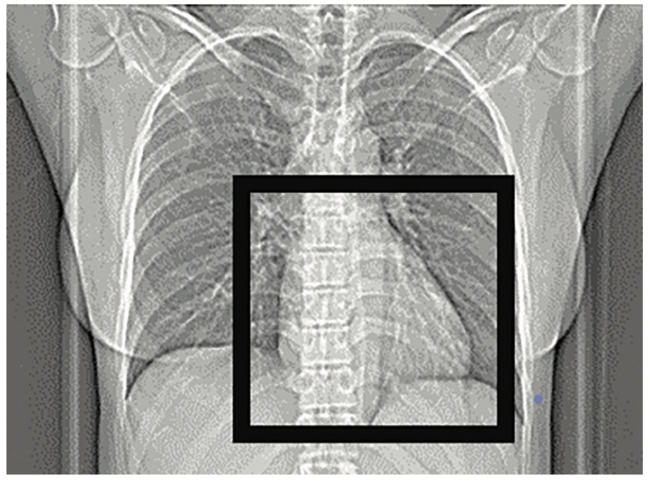

The main limitations of CT calcium scoring are that it is an out-of-pocket expense unless it is authorized by insurance as part of a CCTA exam. There is also potential for incidental findings due to the display field of view that is used to obtain the scan (Figure 2). Since the display field of view covers the heart and much of the mediastinum, incidental extra-cardiac findings have been reported that may lead to unnecessary follow-up studies and treatments.3